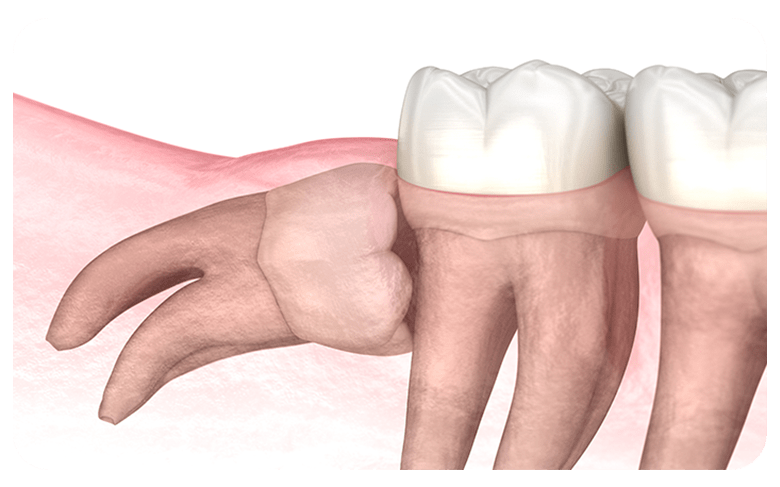

매복사랑니란?

사랑니가 완전히 맹출 되지 않고 잇몸 아래 묻혀있는

형태의 사랑니를  매복 사랑니라고 합니다.

매복 사랑니는 함치성 낭종, 염증 유발, 턱뼈 손상 등의

문제를 유발할 수 있어 발치해 주는 것이 좋습니다.

부분매복

수직매복

원심경사 매복

수평매복

사랑니가 완전히 맹출 되지 않고 잇몸 아래에 묻혀있는 형태의 사랑니를 매복 사랑니라고 합니다.

매복 사랑니는 함치성낭종, 염증 유발, 턱뼈 손상 등의 문제를 유발할 수 있어 발치해주는 것이 좋습니다.